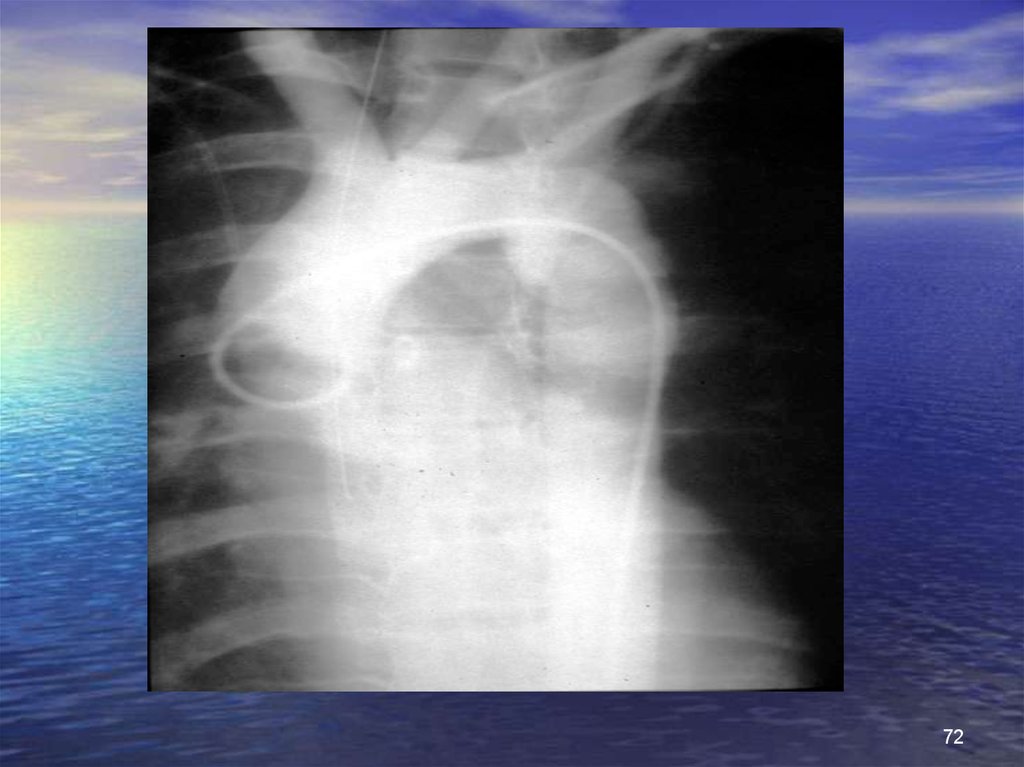

72.

72